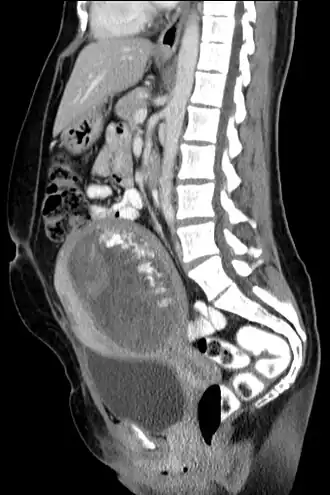

| Tomografia computadorizada, vista sagital. | |